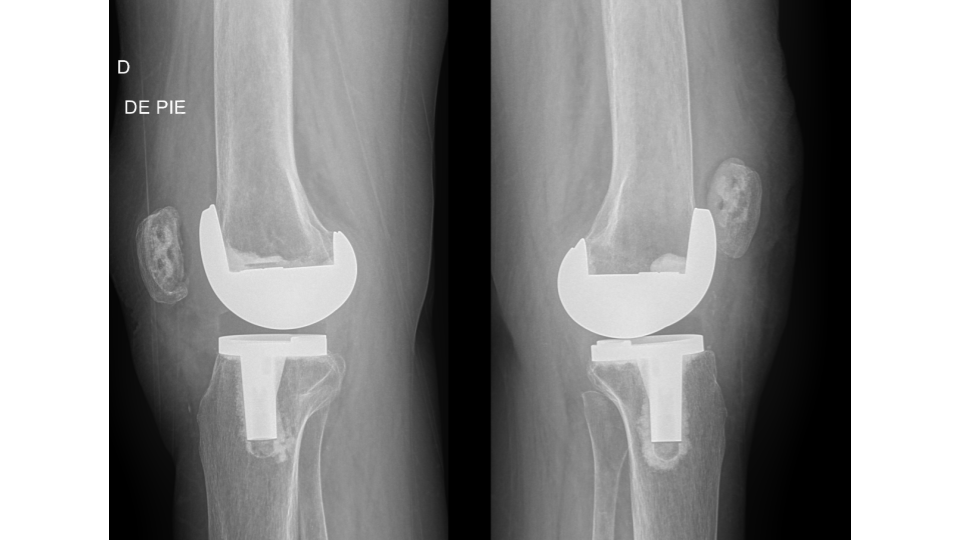

Se analizó un total de 36 prótesis en 32 pacientes. De este total, 25 (78 %) fueron de sexo femenino y 7 (22 %), de sexo masculino. Cuatro pacientes presentaron reemplazo bilateral (Figs. 1, 2 y 3).

Figura 2. Radiografía anteroposterior postoperatoria tras artroplastia total de rodilla con alineación mecánica y prótesis cementada modelo SigmaTM (DePuy, Synthes/Johnson & Johnson, Warsaw, IN, EE. UU.).